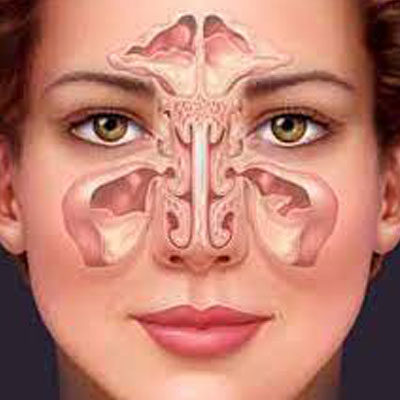

Diseases Treated

Spinal Problems Digestion Diseases Joints & Bones Problems Neurological Diseases Cardiovascular Disorders Respiratory Diseases Thyroid Problems Skin Diseases Diabetes Kidney Problems Male Reproductive Diseases Gyanecological Problems Opthalmic (Eyes) Problems Auto Immune Diseases Children Problems Hair Problems Addiction Rehabilation of Accidential Cases